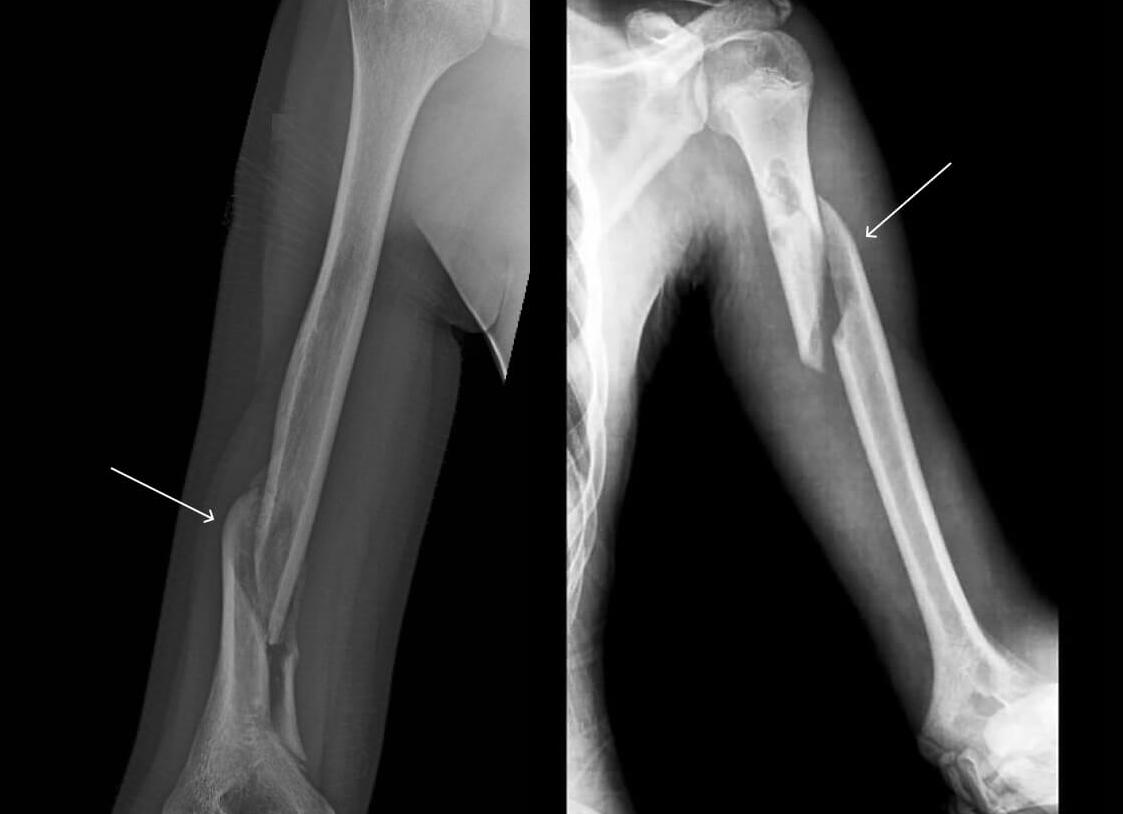

Для уточнения полной картины повреждения врач назначает пострадавшему рентген. Выполняется исследование в двух проекциях. С помощью этого мероприятия удается выяснить состояние носовых костей. Также врач проводит осмотр пациента.